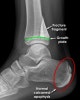

발목관절 골절(Salter-Harris fracture)

A distal tibial fracture passes to the growth plate.

Note the normal unfused calcaneal apophysis which should not be mistaken for a fracture.